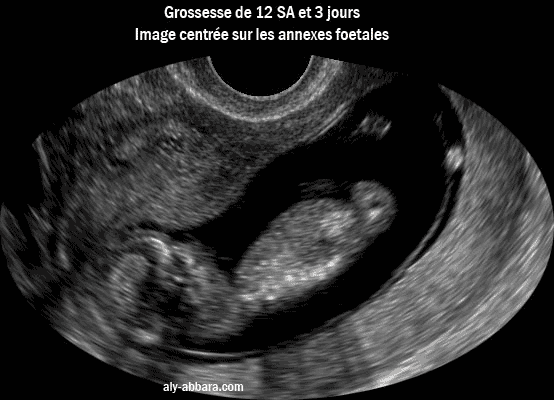

Grossesse de 12,5 semaines d'aménorrhée.

Image échographique montrant les structures embryologiques identifiables à l'échographie :

l'embryon avec son pôle céphalique, son tronc, le sac amniotique, l'amnios, le sac vitellin secondaire "vésicule ombilicale" , le cœlome externe, la cavité choriale, le futur chorion et le futur placenta.